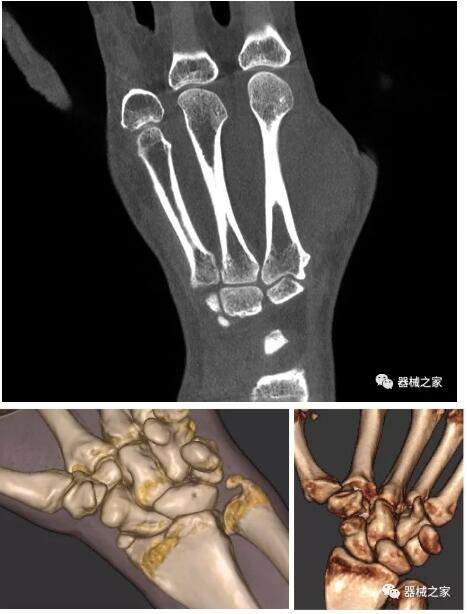

以上介紹的CT均來自國外同一家公司,這些CT均配置了可視化軟件,可以進(jìn)行切片、3D重建以及大型CT附帶的所有典型的操作功能。

以下是這些“特立獨行”的CT所拍出來的圖像: